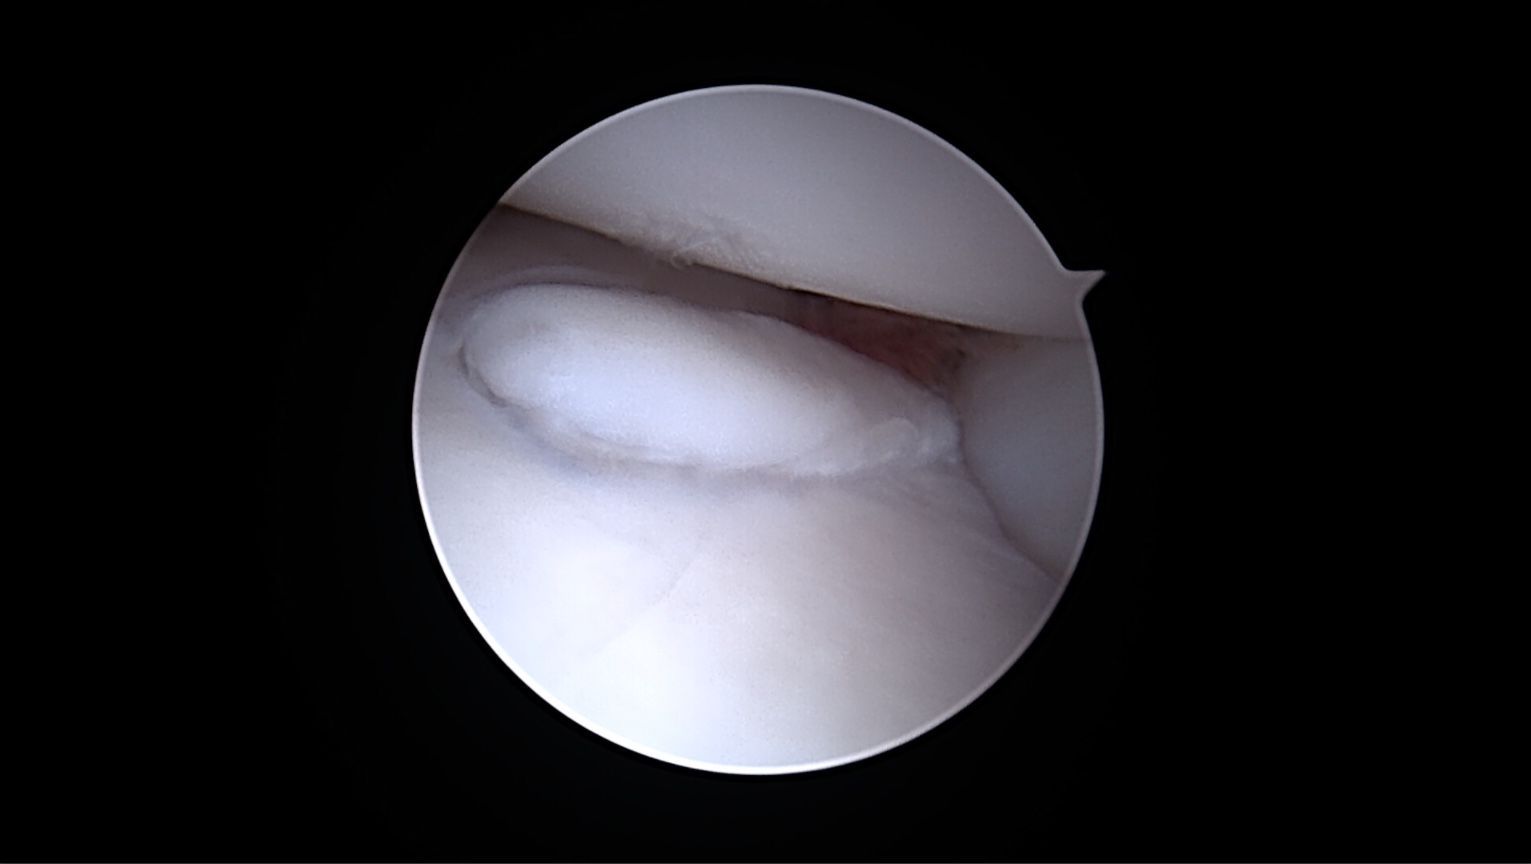

Lésion débutante coronoidienne

Arthroscopie du coude montrant un soulèvement du fragment du processus coronoide médial